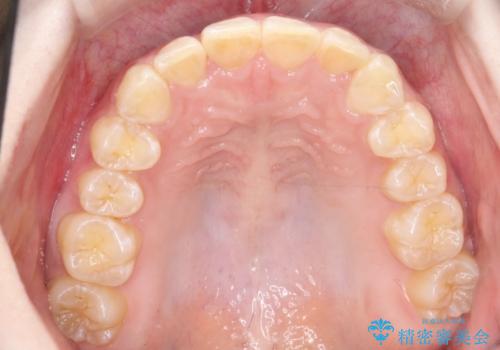

インビザラインで前歯のガタガタをきれいな歯並びへ

上顎の前歯の叢生があったのと、下あごの前歯が通常より1本欠損(先天欠損)していました。

上顎の歯と歯の間をわずかに削りスペースをつくり、並べる計画としました。インビザライン治療を選択されました。

しっかりとインビザラインを使用していただけたので、スムーズに治療を終了させることができました。